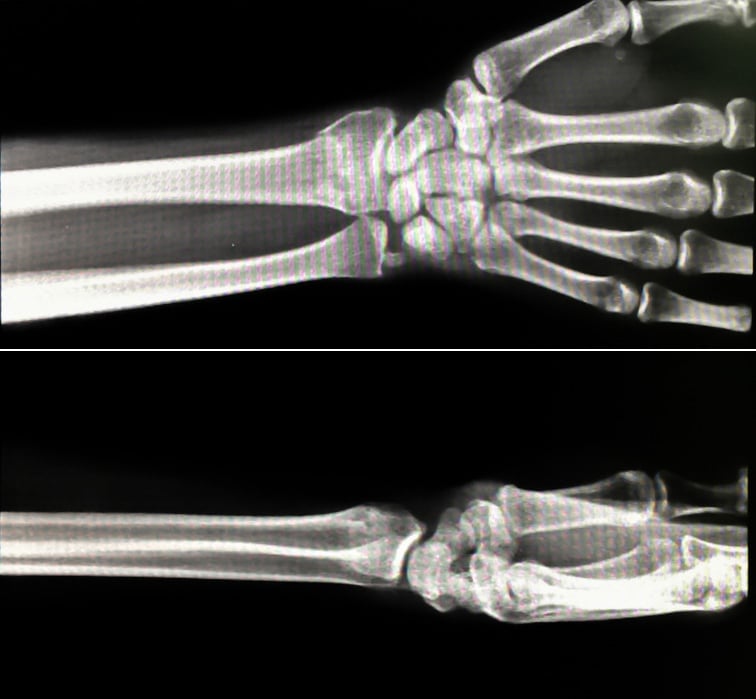

X-rays of a wrist fracture malunion